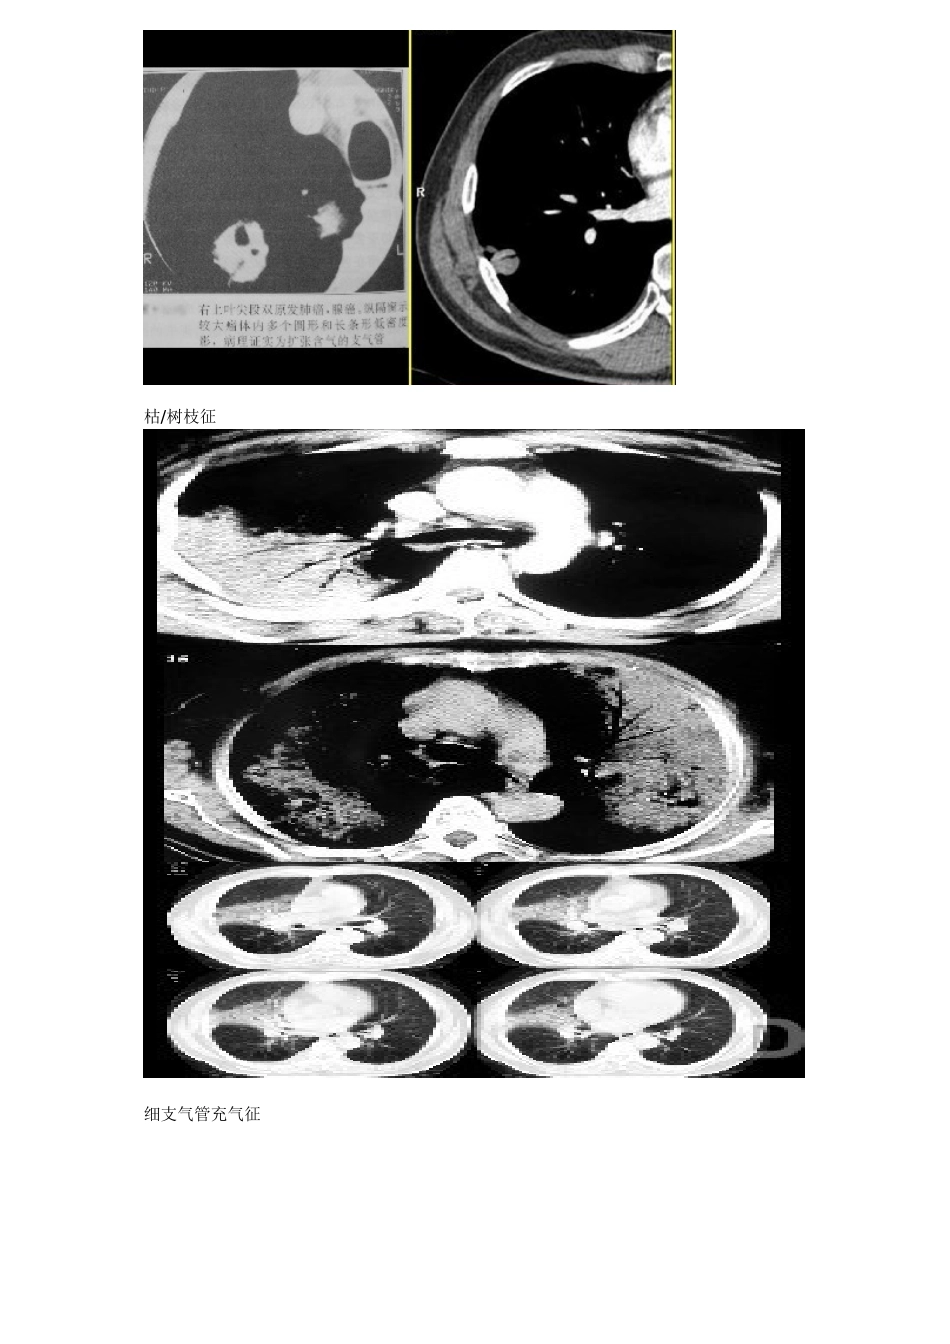

常见胸部 CT 征象1.树芽征(tree-in-bud sign):即小叶核心分布的结节,源于小气道本身的疾病,HRCT 表现为与支气管血管束或小叶核心相连的、直径 3~5mm 大小的结节影、短线状影或分叉状结构。2.印戒征(signet-ring sign):系支气管扩张的典型征象,较大的环状含气影(印戒的指环)为扩张增厚的支气管,其相邻小的软组织影(指环上镶崁的宝石)为伴行的肺动脉影。3.铺路石征(Crazy-paving appearance):系磨玻璃影的背景下同时伴有网格状或细网格状小叶间隔和小叶内间隔增厚。4.界面征(interface sign):血管或支气管等肺实质结构的边缘或肺的胸膜面出现不规则的界面,提示间质增厚。5.支气管充气征(air bronchogram,AB 征):系实变病灶内可见正常充气的支气管或细支气管影,提示气道通畅,而病变位于肺泡。支气管征(小管征、空气支气管征、枯/树枝征、细支气管充气征、病理性支气管像、阳性支气管征、支气管充气征、支气管气像、支气管管征、支气管截断征):是由瘤组织在细支气管与肺泡表面呈伏壁式生长而不充盈管腔,管腔通畅。表现为长、短不一的管状分支状低密度影。可以呈细条状(直径≤1mm)的空气密度影,见于连续数个相邻的层面上,病理上也可以为扩张的细支气管。其发生率也较高,约占 33.3%.在影像上表现可以多种多样,因此名称也较多。支气管征可见于肺癌,肺炎性病变或淋巴瘤。但以肺癌较多见,常与空泡征同时存在,与一般急性炎症空气支气管造影征相鉴别。枯/树枝征细支气管充气征与炎性支气管的鉴别:6.枯枝状支气管充气征:与 AB 征相似,不同点是远端气道被异常软组织填充,充气的支气管树远端稀少呈枯枝状。多见于肺炎型肺泡癌。(同上)7.支气管粘液征(mucous bronchogram):系实变病灶(肺不张)内可见呈低密度的充满粘液的支气管或细支气管影,提示大气道堵塞,其远端被痰粘液充盈。8.CT 血管造影征(CT angiogram sign):CT 增强扫描显示实变病灶内可见高密度的强化肺动脉影,常与支气管粘液征伴行,提示大气道堵塞或实变的组织密度较低。被用来描述大叶型细支气管肺泡癌(腺癌)。是肿瘤沿肺泡壁生长侵润尚未完全破坏肺泡间隔,但使肺泡壁增厚或邻近肺泡内有分泌物,部分肺泡内仍有含气,形成肺炎型改变,增强时可见在病变中穿行的血流强化,称 CT 血管造影征,多见于肺泡癌。当肺血管进入结节或终止结节时,血管常狭窄、堵塞、截断等。文献认为其中以肺静脉包被(肺静脉包被征)...